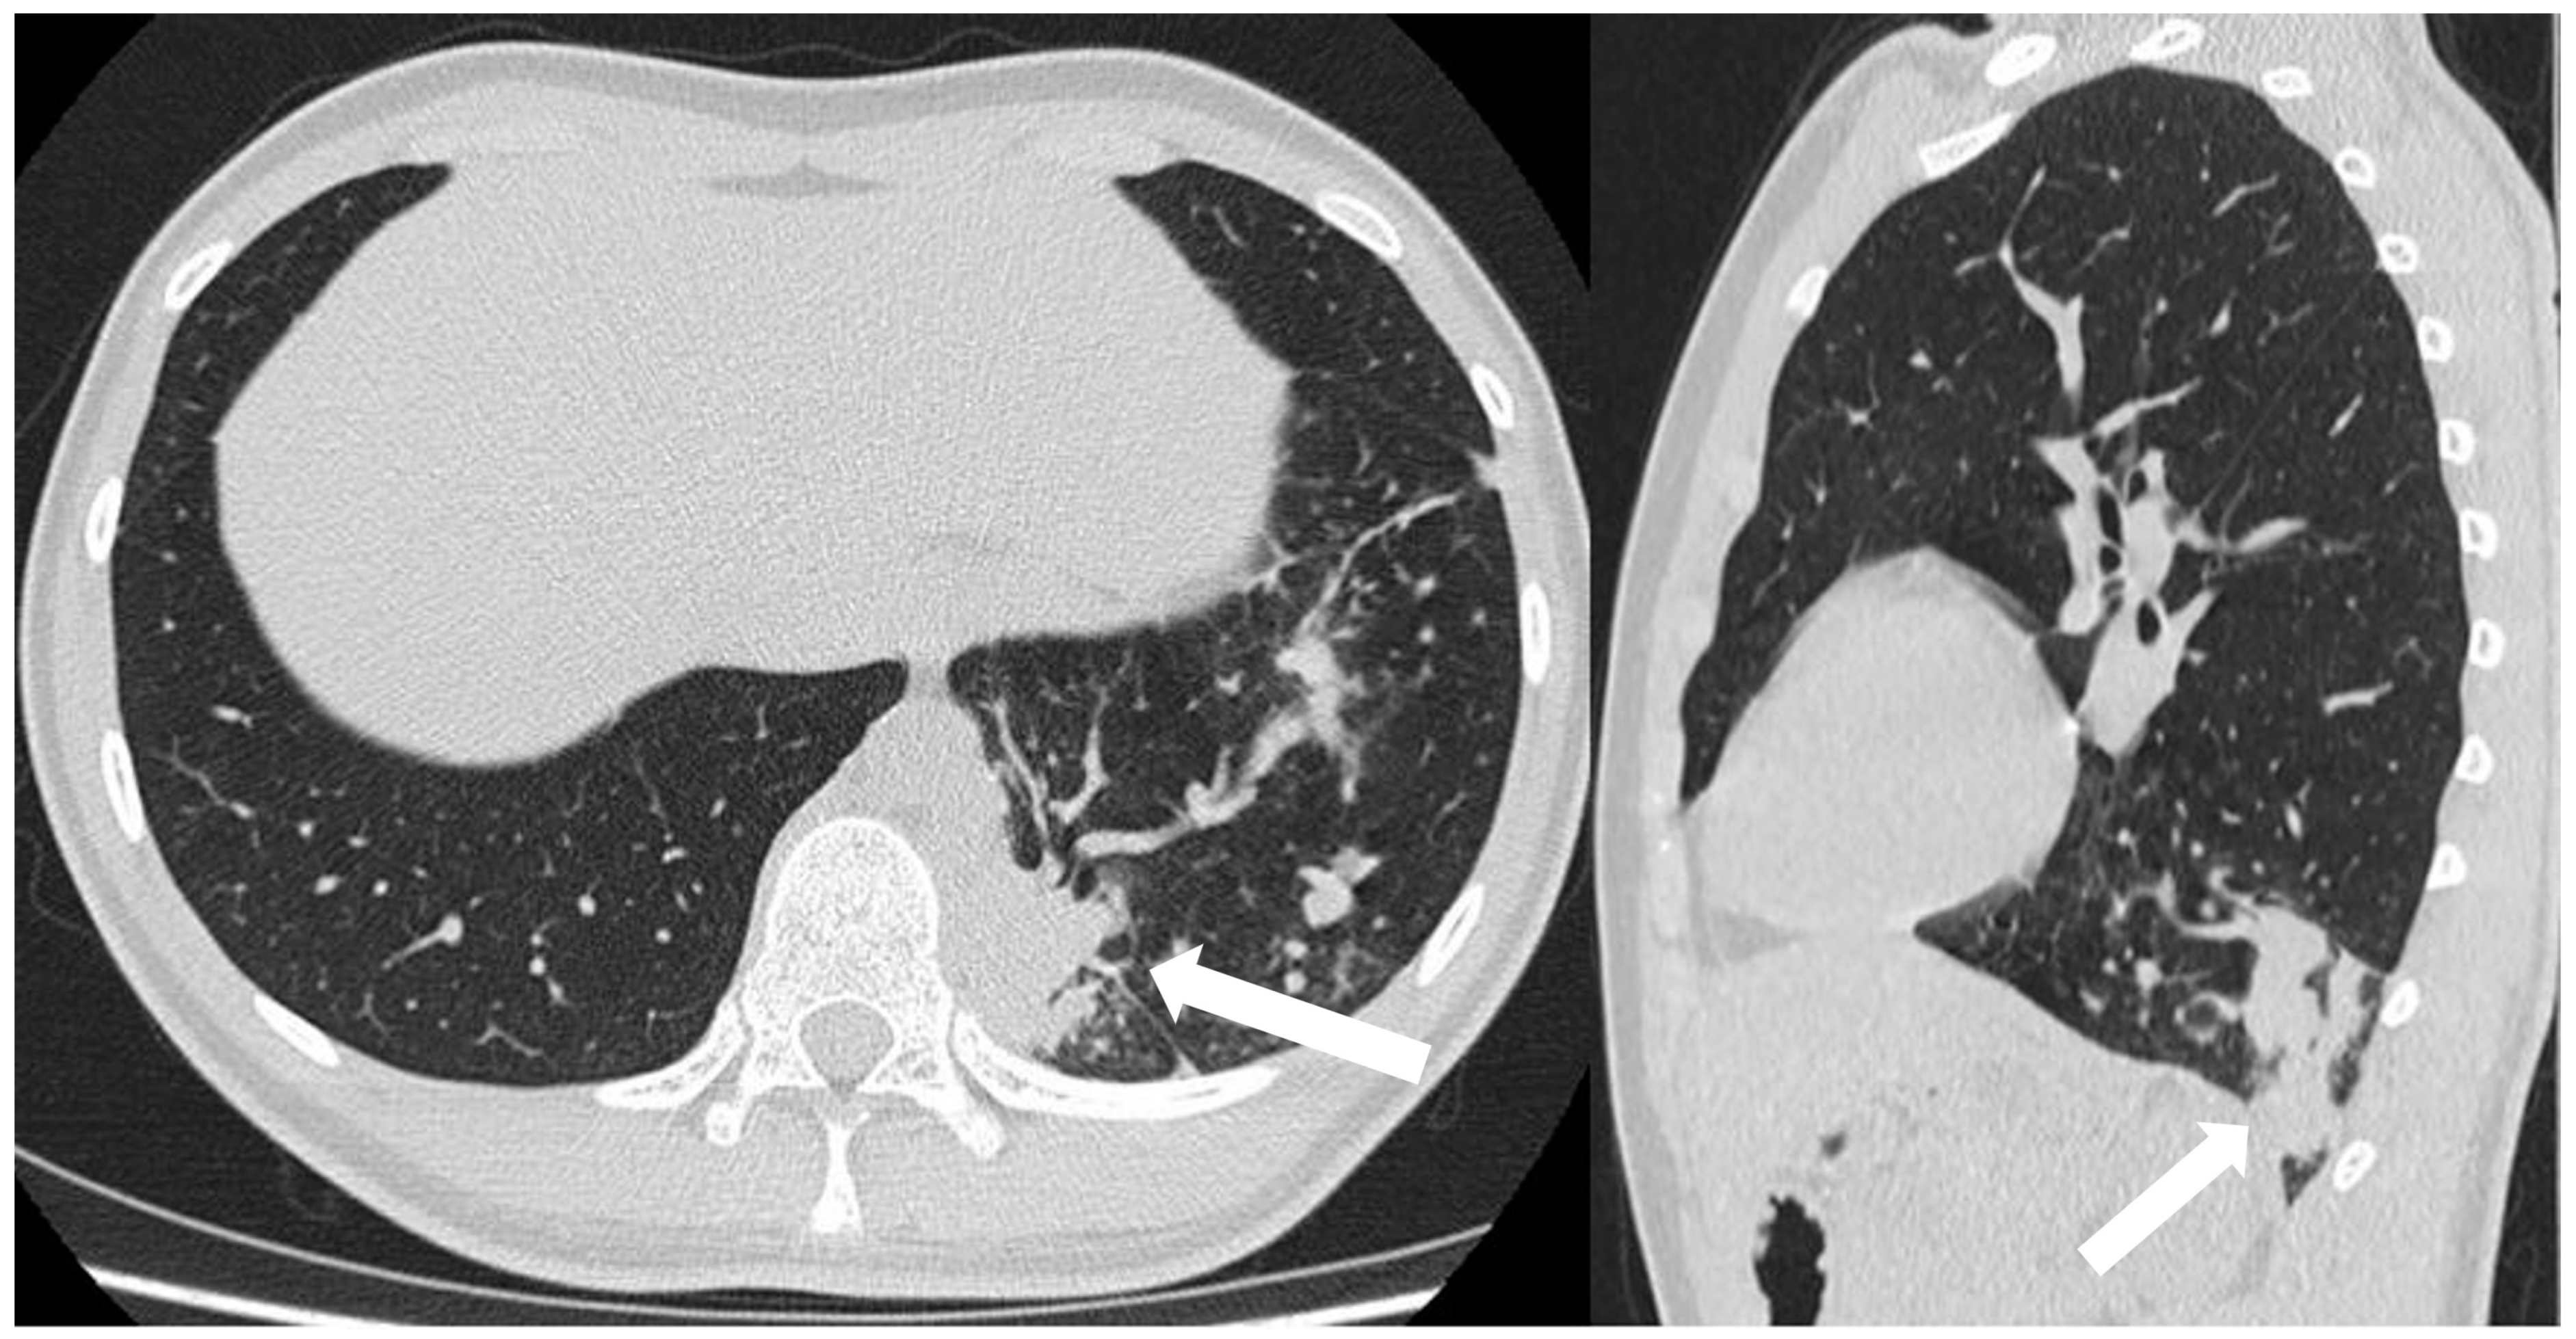

3.6.1. Pulmonary Sequestration